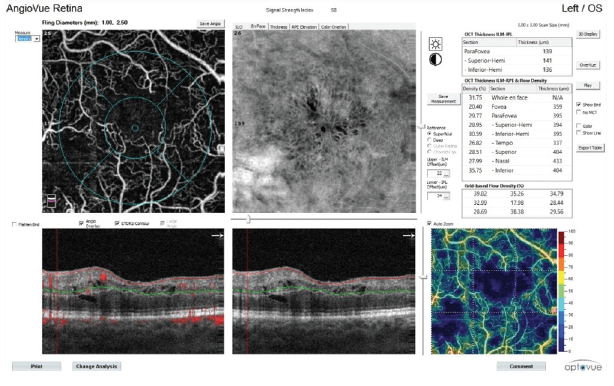

Figure 4. Vessel density analysis in a patient with CRVO.

A helpful step for everyday clinical applications of OCTA has been the development of AngioAnalytics (Optovue), software that provides numerical data about flow area, nonflow area, and vessel density. The flow area measurement tool is useful in the follow-up of choroidal neovascularization (CNV). The operator simply draws the CNV boundary, and the software then calculates the size of the drawn area and vessel area in square millimeters (Figure 2). The nonflow area tool allows clinicians to highlight and monitor the FAZ as well as nonperfused areas in ischemic retinopathies such as DR and retinal vein occlusions (Figure 3). Finally, the vessel density tool automatically calculates the percentage of flow versus nonflow area in an ETDRS grid centered on the macula and in a color-coded vessel density map divided into nine sectors (Figure 4).